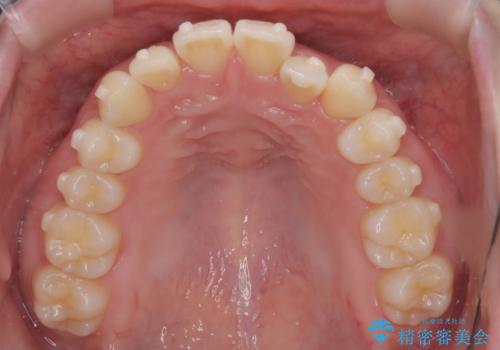

- 左上2の反対咬合(交叉咬合)をインビザラインを用いて治療しました。反対咬合は、歯列の不正咬合の一つであり、上の歯が下の歯よりも内側に位置する状態です。反対咬合は咀嚼や発音に影響を与えることがあります。

左上2の反対咬合をインビザラインで治療する際に、IPR(Interproximal Reduction)を行いました。 IPRとは、隣接する歯の間のエナメル質をわずかに削る手法で、歯の幅を減少させることによって歯列を整える技術です。